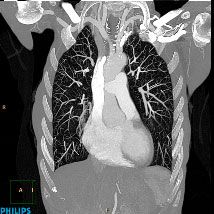

CT screening for lung cancer could save thousands of lives if routinely covered by insurers, according to a Health Affairs study.

There was concern that cancers diagnosed in routine screening were less aggressive than those found in routine practice.

New guidelines that call for lower radiation exposure from CT-guided biopsies of lung nodules allows more people to undergo the procedure and may result in fewer overall lung cancer deaths.